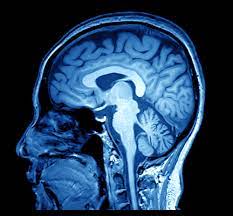

La neuroradiologie est une sous-spécialité de la radiologie, spécialisée dans l'imagerie diagnostique du cerveau, de la colonne vertébrale, de la tête et du cou.

Les principales modalités d'imagerie sont la tomodensitométrie (Scanner) et l'imagerie par résonance magnétique (IRM).